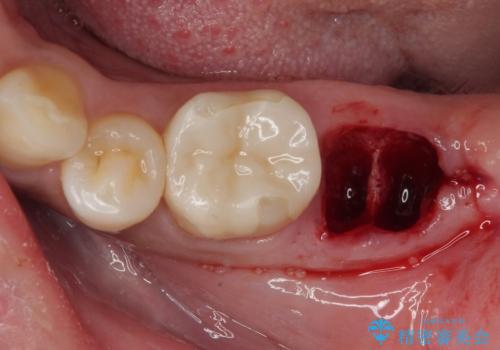

- 他院で「左下の親知らずの手前の歯が虫歯」と診断された患者様の症例です。

診査の結果、下顎左側第二大臼歯の遠心(奥側)に大きな虫歯があり、歯肉の奥深く、骨の縁まで進行している状態でした。

このようなケースでは、虫歯を完全に除去して精密な補綴治療をするのが難しく、長期的な予後が不良となることが多いです。

そこで今回は、抜歯即時インプラントの適応と判断しました。